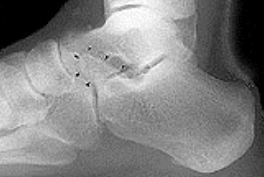

| What do the arrows show? | Stress fracture |